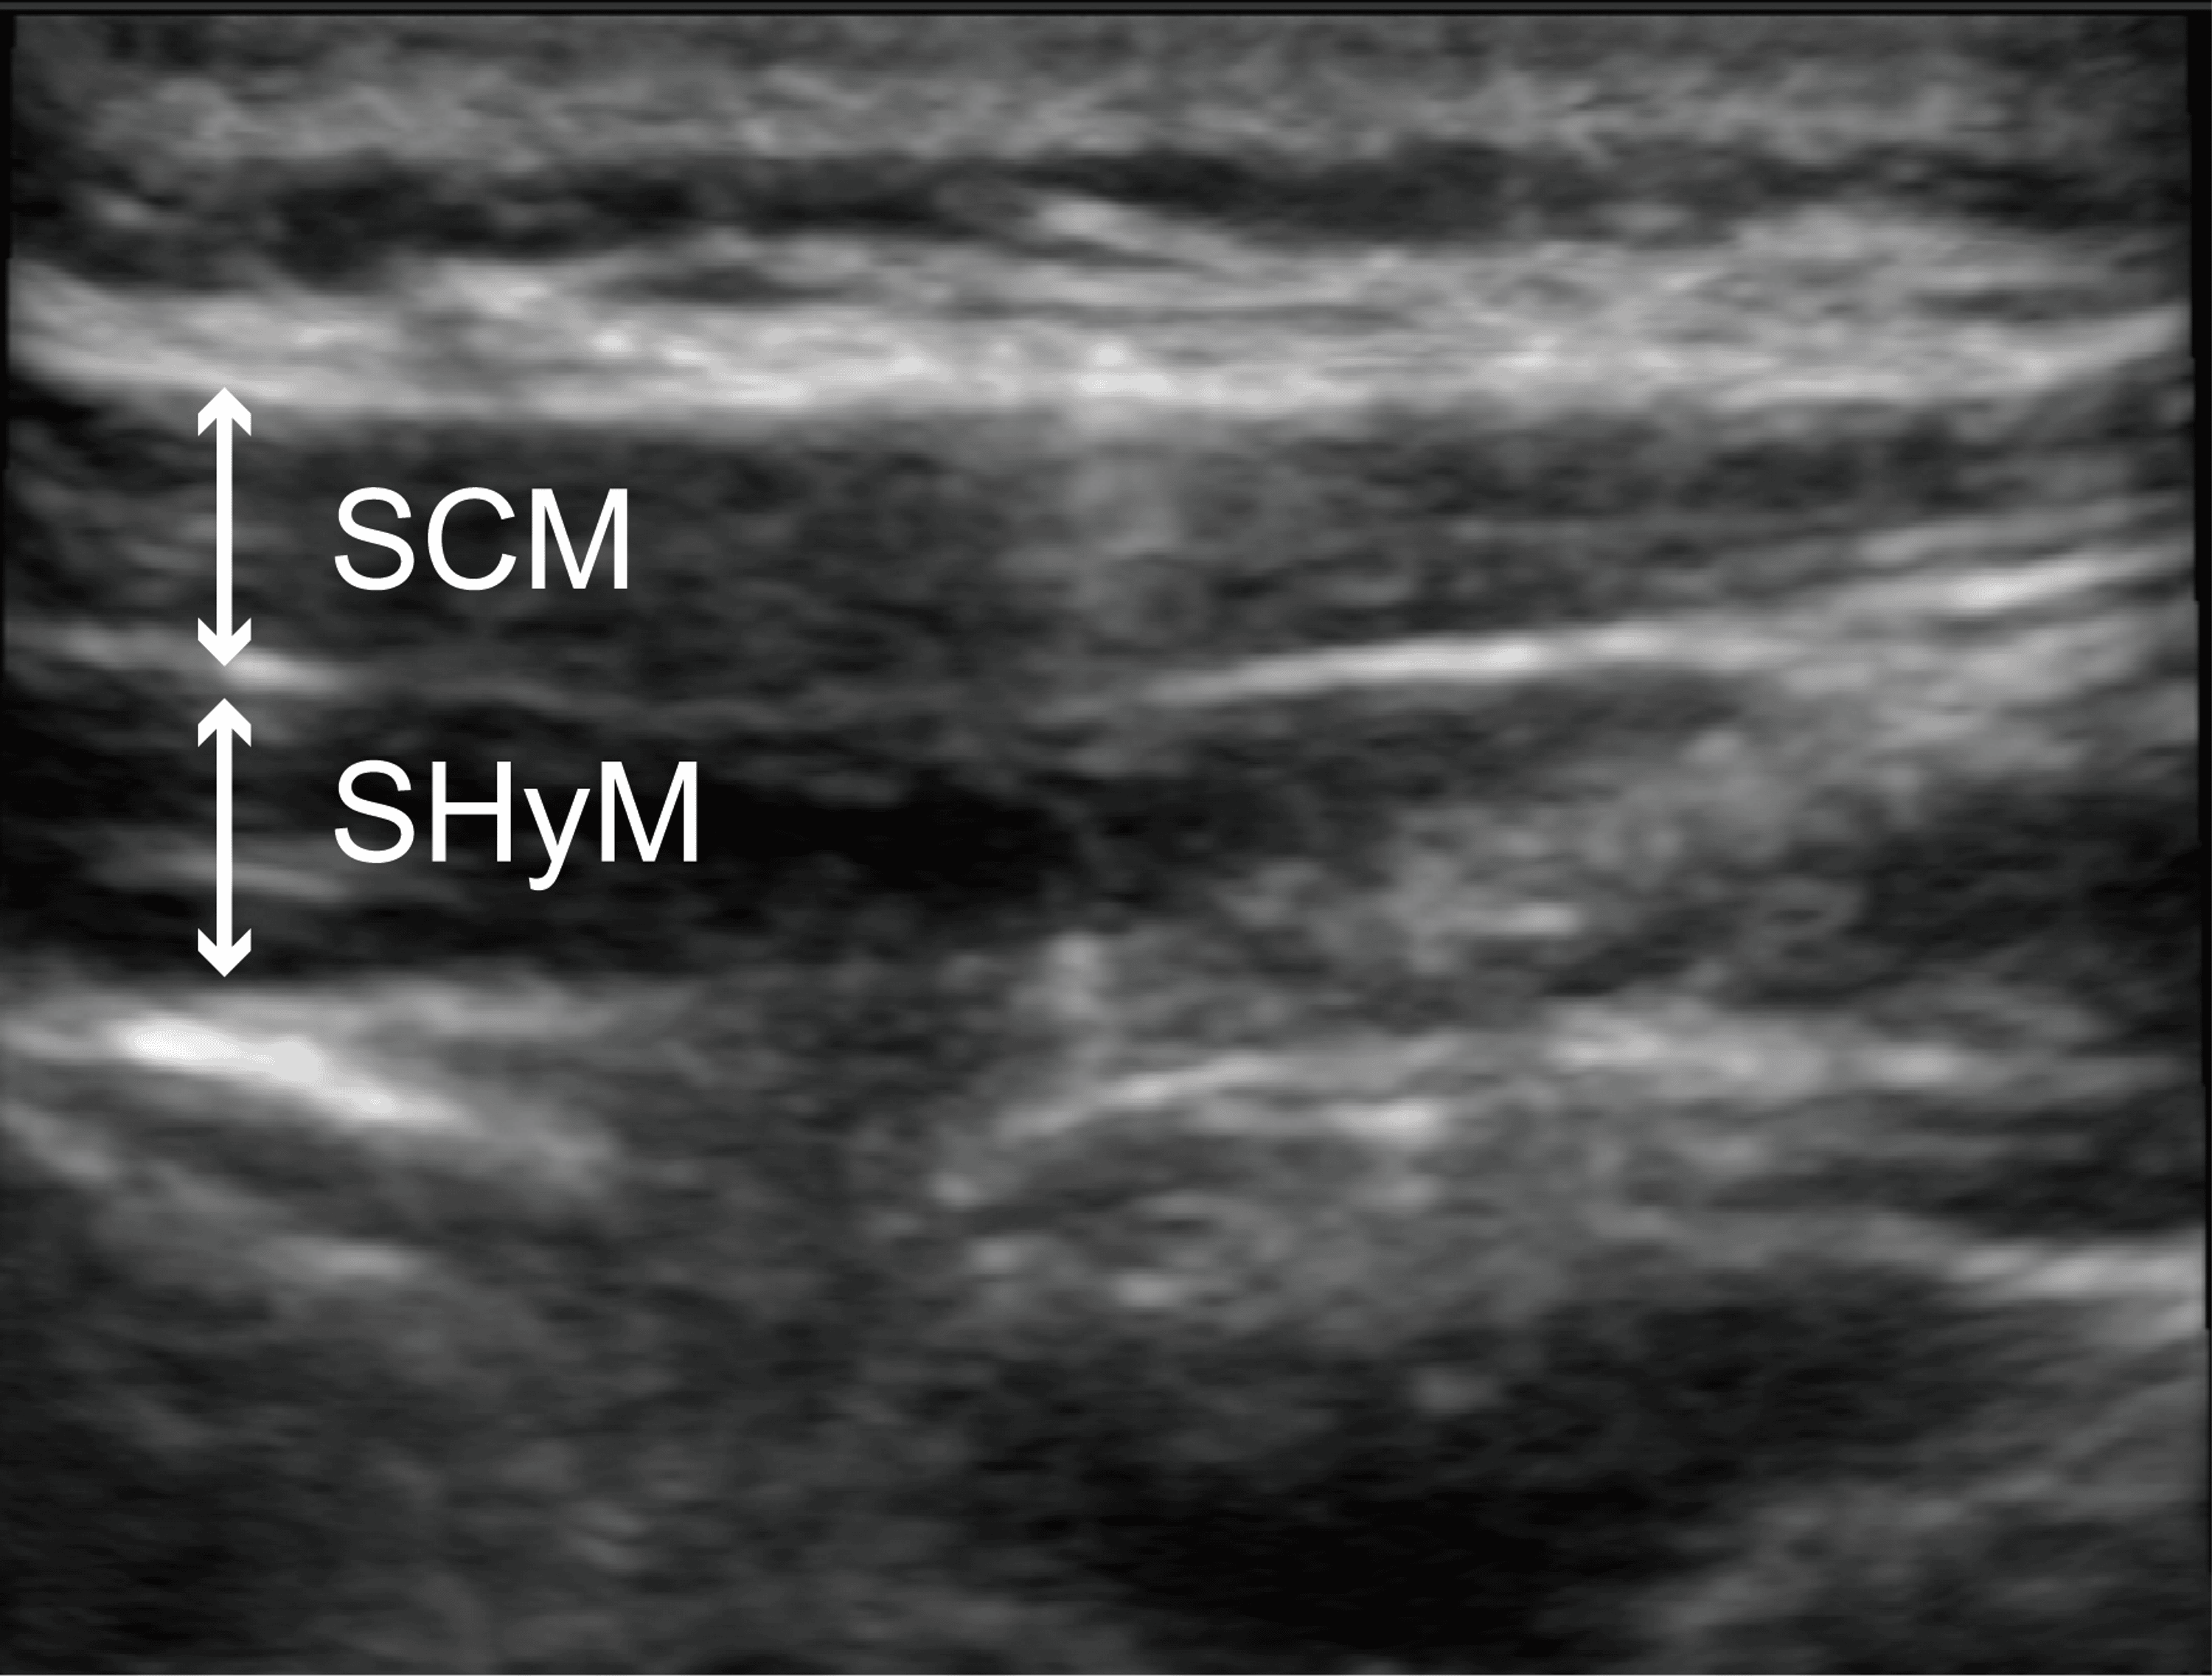

From www.cureus.com

UltrasoundGuided Selective Glossopharyngeal Nerve Block for Severe Gag Glossopharyngeal Nerve Block For Pain Relief We investigated the role of perioperative intraoral glossopharyngeal nerve block to minimize postoperative pain in. The glossopharyngeal nerve block (gpnb) is used primarily in pain management in cases of neuralgia as well as to abolish the gag reflex for. Twelve patients completed a total of 48 injections for glossopharyngeal nerve block. The mean procedure time was 9.51±0.89 mins. A modification. Glossopharyngeal Nerve Block For Pain Relief.

From www.researchgate.net

(PDF) Ultrasoundguided Glossopharyngeal Nerve Block A New Paradigm in Glossopharyngeal Nerve Block For Pain Relief The glossopharyngeal nerve block (gpnb) is used primarily in pain management in cases of neuralgia as well as to abolish the gag reflex for. A regional anesthetic technique formerly used in adults for tonsillectomy was adapted to provide posttonsillectomy pain relief in. A modification of this technique, termed glossopharyngeal nerve block (gnb), which uses bupivacaine, was introduced at our institution.. Glossopharyngeal Nerve Block For Pain Relief.

From journals.lww.com

UltrasoundGuided Glossopharyngeal Nerve Block for an Awake... A&A Glossopharyngeal Nerve Block For Pain Relief Twelve patients completed a total of 48 injections for glossopharyngeal nerve block. A regional anesthetic technique formerly used in adults for tonsillectomy was adapted to provide posttonsillectomy pain relief in. A modification of this technique, termed glossopharyngeal nerve block (gnb), which uses bupivacaine, was introduced at our institution. We investigated the role of perioperative intraoral glossopharyngeal nerve block to minimize. Glossopharyngeal Nerve Block For Pain Relief.